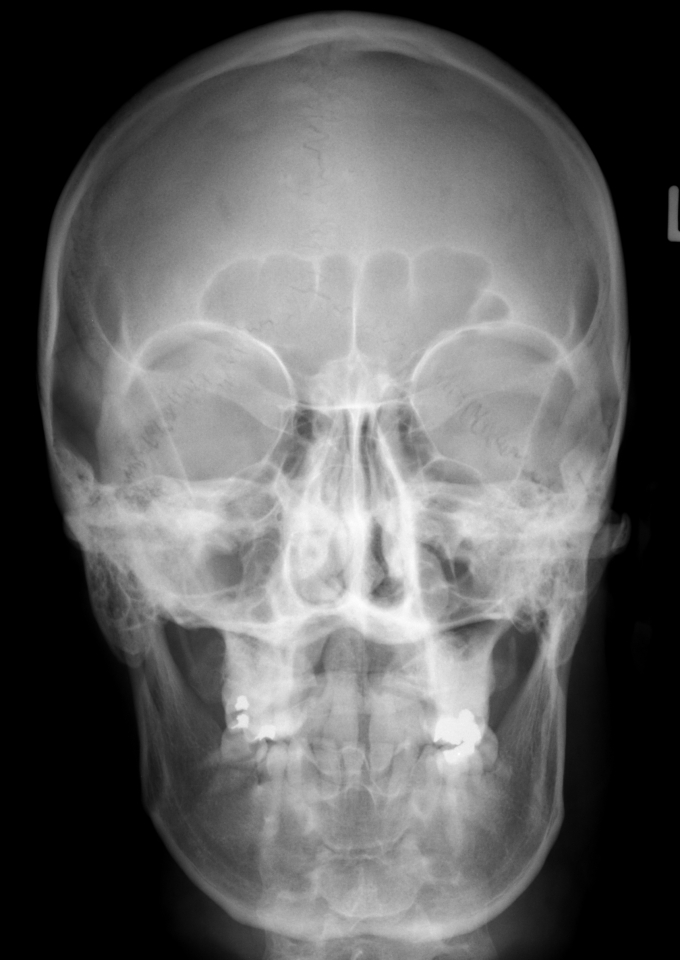

56 year old patient with dyspagia. A tumor of soft tissue was described in upper mediastinum on plain X-ray of the thorax. What is this mass in the upper mediastinum?